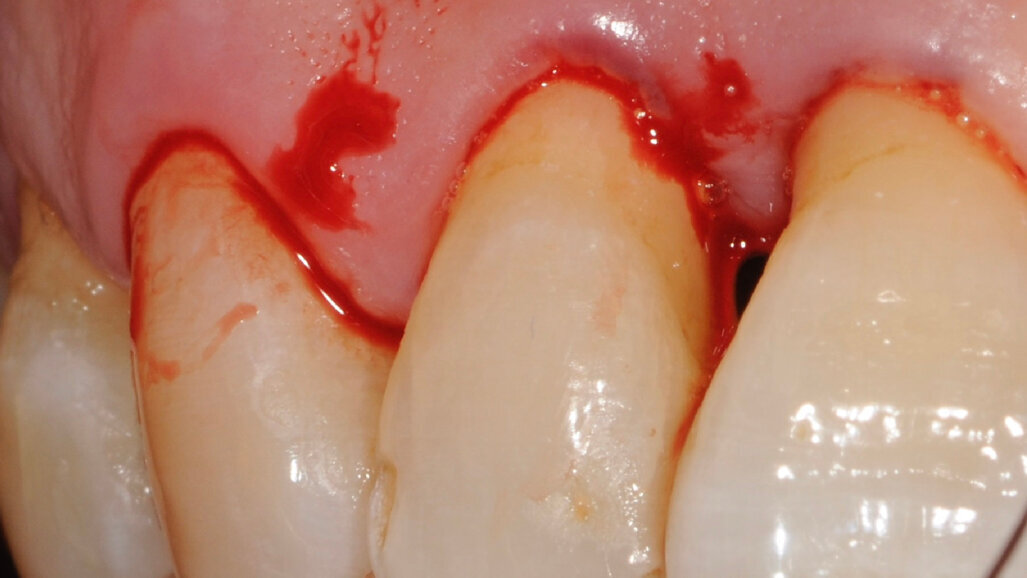

Un paziente di 56 anni non fumatore viene riferito alla nostra osservazione per il trattamento della parodontite. Dopo aver effettuato la diagnosi (parodontite generalizzata Stadio III, Grado C) il paziente è sottoposto a due sedute di scaling sopra gengivale (step 1) e successivamente a 4 sedute di debridement sotto gengivale effettuato con strumenti ultrasonici e manuali (step 2). Al momento della rivalutazione si registra un miglioramento degli indici di placca e di sanguinamento (FMPS e FMBS ≤ 20%) e una riduzione di tutte le tasche parodontali (PD<4 mm) in ciascun sestante a eccezione del secondo sestante. In questa regione si registra una tasca residua con PD = 6 mm a carico dell’elemento 1.1, associata a un riassorbimento osseo radiografico prevalentemente orizzontale (Figg. 1, 2). Considerando il miglioramento di tutti i parametri e degli indici parodontali e la presenza di una tasca con PD = 6 mm a carico di un solo elemento dentario si decide di ritrattare l’elemento 1.1 con terapia non chirurgica (step 3). La nuova ristrumentazione è stata effettuata seguendo il protocollo Clean&Seal che prevede l’associazione di ipoclorito di sodio stabilizzato con amminoacidi e acido ialuronico reticolato ad alto peso molecolare in combinazione con il debridement sotto gengivale. Dopo anestesia locale, è stato applicato all’interno della tasca l’ipoclorito di sodio stabilizzato con amminoacidi e lasciato agire per circa 60 secondi (Fig. 3). Successivamente è stata effettuata la strumentazione sotto gengivale mediante l’utilizzo di strumenti ultrasonici e manuali (Figg. 4, 5). Alla fine della procedura di strumentazione, nella tasca è stata effettuata un’irrigazione con soluzione salina sterile e la procedura di applicazione di ipoclorito di sodio e di strumentazione meccanica è stata ripetuta per 4 volte. Un fattore critico per garantire un risultato migliore è di evitare di instillare qualsiasi soluzione a base di clorexidina nella tasca, in quanto inibisce l’adesione cellulare. Alla fine del trattamento meccanico è stato inserito l’acido ialuronico reticolato ad alto peso molecolare all’interno della tasca per stabilizzare il coagulo e accelerare la guarigione (Fig. 6). Il controllo clinico è stato effettuato dopo 6 settimane dal trattamento con completa chiusura della tasca (Fig. 7).